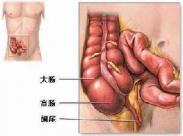

腹裂

628健康网为您分享有关腹裂的症状,腹裂的治疗方法,腹裂的预防知识,腹裂的症状图片,腹裂吃什么药,腹裂怎么治疗,腹裂患者食...

脐膨出

628健康网为您分享有关脐膨出的症状,脐膨出的治疗方法,脐膨出的预防知识,脐膨出的症状图片,脐膨出吃什么药,脐膨出怎么治...

外伤性脾破裂

628健康网为您分享有关外伤性脾破裂的症状,外伤性脾破裂的治疗方法,外伤性脾破裂的预防知识,外伤性脾破裂的症状图片,外...